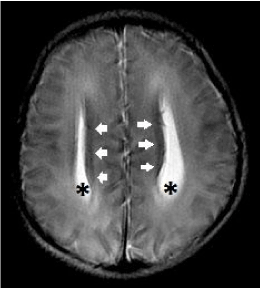

In primary callosal agenesis, white matter tracts that normally cross the midline to form the corpus callosum now reside along the superomedial wall of the lateral ventricles, giving rise to the callosal bundles of Probst. Therefore, the presence of Probst bundles is a strong evidence of primary callosal agenesis (Figure 14 a-c).

Figure 14. Complete primary agenesis of the corpus callosum. Axial T2-weighted image shows colpocephaly (*) and the presence of Probst bundles (white arrows) along the medial margins of the widely spaced lateral ventricles.